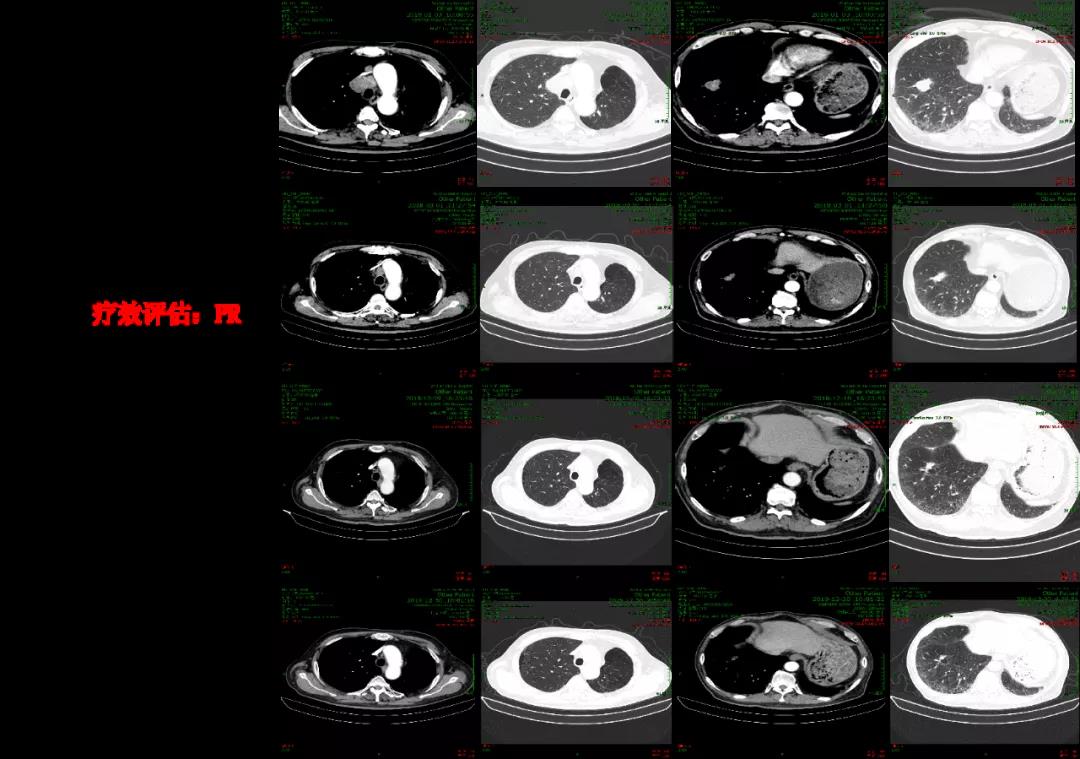

2018年3月第一次疗效评估即达到PR,2018年6月开始行维持治疗,至2020年1月维持治疗结束。2020年5月随访结果显示患者仍然保持病情稳定,PFS已达28个月(图3)。

本例患者为59岁男性,诊断为右下肺低分化腺癌(EGFR和ALK基因阴性,PD-L1阳性)。患者自愿入组CameL研究后,进入治疗组接受“卡瑞利珠单抗+培美曲塞+卡铂”一线治疗,治疗仅1周期即达到PR,此后接受“卡瑞利珠单抗+培美曲塞”维持治疗,PFS达28个月,目前仍保持病情稳定,持续随访中。总的来说,卡瑞利珠单抗一线联合化疗治疗野生型晚期肺腺癌疗效显著,可实现生存期显著延长,且安全耐受性好,患者生活质量显著提高。